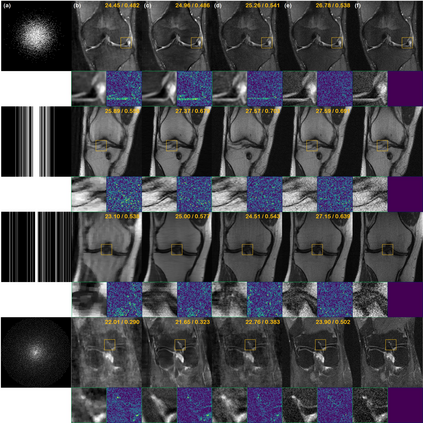

Score-based diffusion models provide a powerful way to model images using the gradient of the data distribution. Leveraging the learned score function as a prior, here we introduce a way to sample data from a conditional distribution given the measurements, such that the model can be readily used for solving inverse problems in imaging, especially for accelerated MRI. In short, we train a continuous time-dependent score function with denoising score matching. Then, at the inference stage, we iterate between numerical SDE solver and data consistency projection step to achieve reconstruction. Our model requires magnitude images only for training, and yet is able to reconstruct complex-valued data, and even extends to parallel imaging. The proposed method is agnostic to sub-sampling patterns, and can be used with any sampling schemes. Also, due to its generative nature, our approach can quantify uncertainty, which is not possible with standard regression settings. On top of all the advantages, our method also has very strong performance, even beating the models trained with full supervision. With extensive experiments, we verify the superiority of our method in terms of quality and practicality.